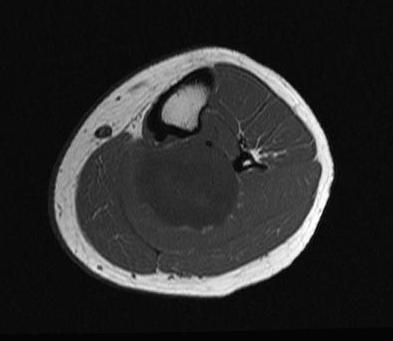

MRI

Target sign

- hypointense centrally

- hyperintense peripherally